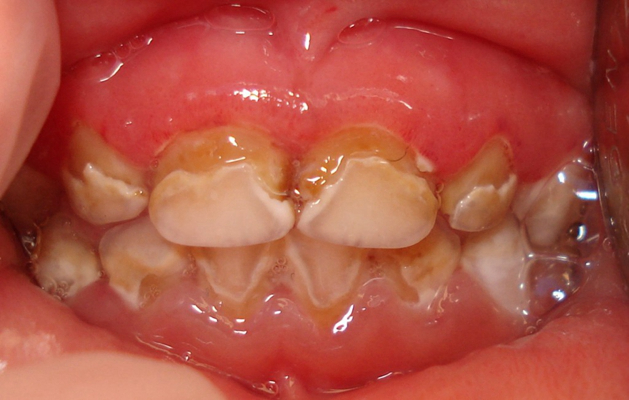

牙齦炎圖片

牙齦炎和牙周炎